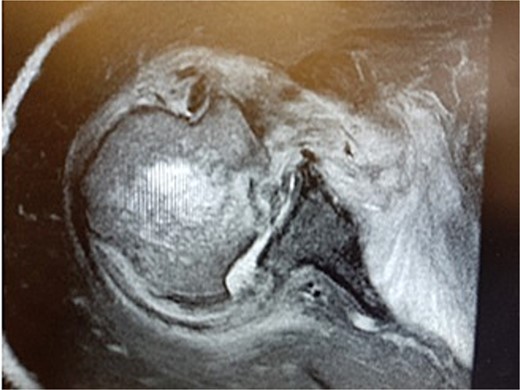

During the outpatient follow-up visit at the Orthopedic Clinic, ~10 weeks after the accident, a physical examination of the patient was conducted, which included shoulder X-ray imaging. The examination revealed severe pain in the right shoulder and a significant limitation in the mobility of the joint (results summarized in Table 1). The above enforced the decision of expanding the imaging diagnostics to look for fractures within the humeral head; hence, computed tomography (CT) and magnetic resonance imaging (MRI) examinations of the right shoulder were carried out. Additional imaging studies revealed a depression fracture of the humeral head covering 2/3 of the articular surface with posterior subluxation of the right shoulder joint. The examination also revealed that the continuity of the tendons of the rotator cuff muscles has been preserved.

MRI images can be found in Figs 3 and 4, and CT images in Fig. 5.